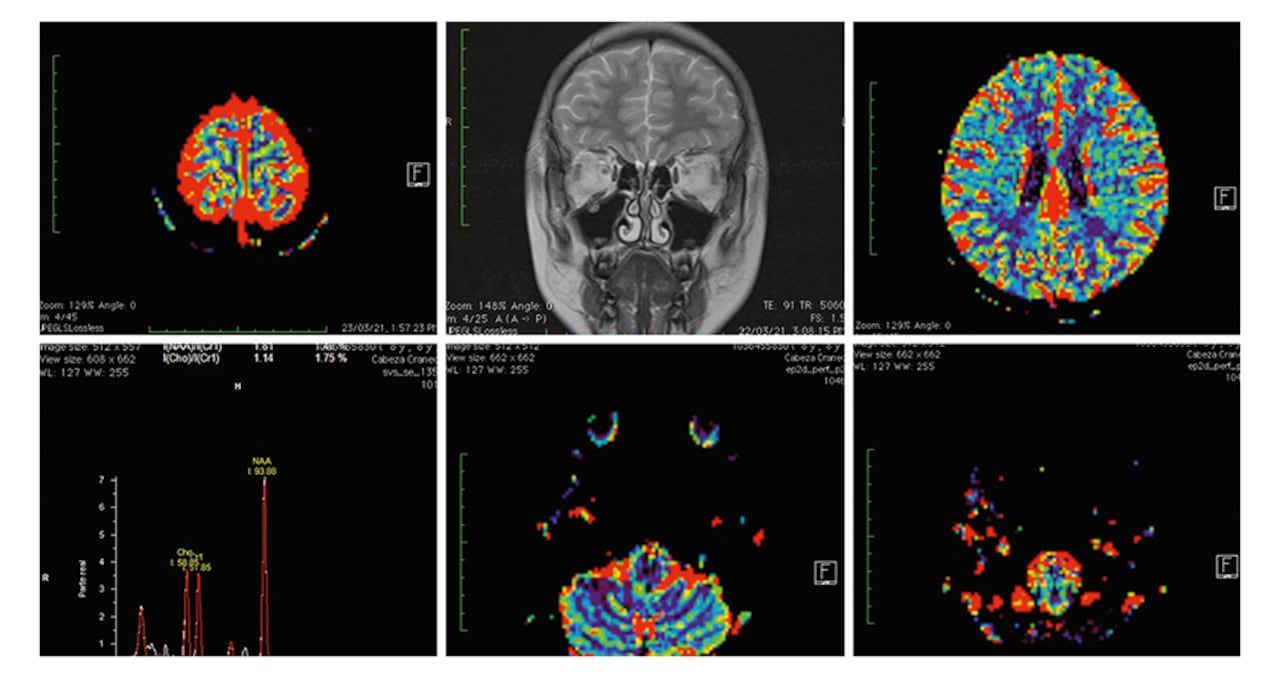

Los índices de hurto bajaron significativamente. ¿Pero qué pasó por la mente del criminal para causar el efecto disuasivo? Los expertos recrearon escenarios criminales en los que participaban personas que no habían cometido delitos y delincuentes condenados. A cada uno les conectaron unos electrodos en su cabeza. Sentado frente a un monitor de computador, uno de los investigadores revisa las reacciones del cerebro en cada uno de los escenarios. El experto observa un gráfico de frecuencias que se activa con cada parte del cerebro estimulado. Centra su atención en el sistema límbico, ligado con los instintos humanos, la memoria involuntaria, el hambre, la atención, los deseos sexuales y las emociones como el placer, el miedo y la agresividad.

Esta zona determina la personalidad y la conducta de cada ser humano. Así, analizaron la mente de ladrones de celulares y de otros objetos, así como de personas dedicadas al microtráfico, extorsiones y estafas. Concluyeron que cuando realizan estas actividades, se estimula el mesencéfalo, que crea mecanismos de recompensa en el cerebro. Es decir, cuando un ladrón sabe que el beneficio es mayor que el riesgo asumido, siente el impulso de cometer el delito. Pero también identificaron el momento exacto en el que el criminal siente miedo.

En el momento en que eso pasa, el investigador ve cómo la imagen de la frecuencia se dispara con mayor velocidad. Eso le indica que la amígdala cerebral genera señales de alerta que le producen miedo. La amígdala es el principal núcleo de control de las emociones y sentimientos en el cerebro. Su vinculación con el lóbulo frontal hace que el delincuente se abstenga de actuar. La sensación que experimenta es la misma que vive alguien que se sube al piso 20 de un edificio y mira hacia abajo.